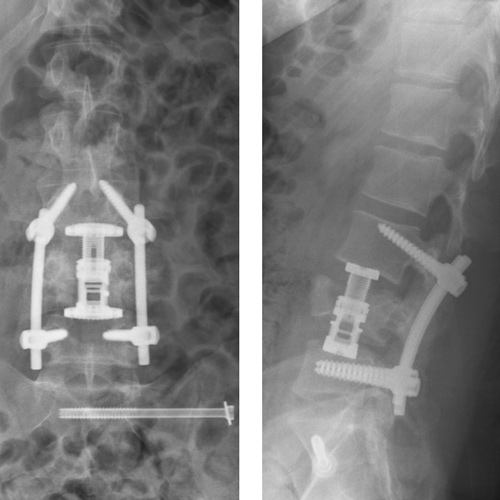

Spinal stenosis (Lumbar) Spinal stenosis (Cervical) Spinal stenosis (Thoracic) Lumbar Disc Herniation Spondylolisthesis Cervical Foraminal Stenosis Vertebroplasty Lumbar Fusion Anterior Cervical Fusion (ACDF) Posterior Cervical Fusion Thoracic Fusion Revision Lumbar Fusion Surgery Facet Joint Cyst Spinal Tumour Minimally Invasive Lumbar Fusion (XLIF) Minimally Invasive Lumbar Fusion (ALIF) Lumbar Fusion (TLIF) Thoraco-lumbar Fusion Lumbar Corpectomy Complex Lumbar Spine Surgery (Spino-pelvic fixation) Complex Cervical Spine Surgery Complex Thoracic Spine Surgery Occipito-cervical Fusion Minimally invasive surgery for thoracic disc herniation Other Related Topics